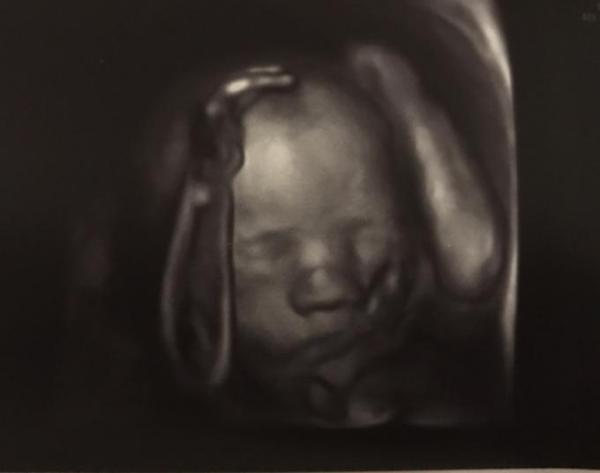

Huhu Mädels, Also ich war ja gestern wegen vermehrt Fruchtwasser bei der feindiagnostik.. nach über ner Stunde warten kamen wir endlich dran (gegen halb 9 abends ). Naja er hat sich jedenfalls dennoch sehr viel Zeit genommen, bestimmt ne halbe Stunde geschallt und die Maus von Kopf bis Fuß komplett durchgecheckt. Mit dem Baby alles top, alles gut entwickelt, gut durchblutet, kein Hinweis auf fehlbildungen oder Störungen am Kind oder der Plazenta etc. Madame hat etwa 30cm und 788g. Er war sehr zufrieden mit allem. Wegen dem vermehrten Fruchtwasser sagte er, dass die Ursache in etwa 60% der Fälle unklar bleibt. Das muss jetzt halt regelmäßig kontrolliert werden, in zwei Wochen soll ich wieder kommen und er will nochmal schauen ob es mehr geworden ist/unverändert/weniger oder sonst was. Er meinte auch noch, dass wir eine Fruchtwasserpunktion maxhenlassen könnten, allerdings würde er uns aktuell nicht dazu raten. Sollte es irgendwann dazu kommen und viel zu viel Fruchtwasser sein, muss es abgelassen werden und er meinte dann könne man immer noch eine Probe entnehmen. Hoffe dass ich da drumherum komme und es sich entweder reguliert oder einfach nur unerklärt vermehrt bleibt. So und sehr zu unserer Freude, haben wir (wie schon beim ersttrimester Screening bei ihm) wieder eine ganze amada von Bildern (auch 3D) bekommen.. von Händen, Gesicht, Geschlecht, etc. Und den 3D Termin für in zwei Wochen sage ich auch wieder ab. Die 130€ sparen wir uns

Bild zu Gestern feindiagnostik  - Forum für August - Mamis

Da hat das Gerät wohl vergessen ein bisschen Fleisch über die Unterarm Knochen zu legen sehr geiles Bild! Und gut dass alles ok ist ich hatte bis zum Schluss immer viel zu viel fruchtwasser und es wurde eigentlich nie etwas daran gemacht oder so also ist doch super das es abgeklärt wurde

Was für ein tolles Bild!!!! Wunderschön Es ist doch erst mal beruhigend, dass es soweit ok ist. Da freue ich mich sehr für euch

WOW - was ein schönes Bild! Klasse! Schön, dass mit der Maus alles okay ist. Und wegen des FWs würde ich mir keine Gedanken machen. Lieber zu viel als zu wenig. Wirst gegen Ende immer engmaschiger kontrolliert, denke ich...

Super das soweit alles gut ist!!!! Und wunderschönes Bild

Wunderschönes Bild! Wie weit bist du? Ich hatte auch immer zuviel FW, wurde nix gemacht. Eure Maus würde gut durchgecheckt; das ist das wichtigste!